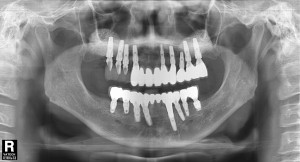

치료 중 찍은 방사선 사진입니다.

치료 필요에 따라 뼈이식도 진행하였습니다.